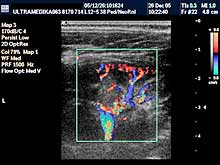

Pregled dece zahteva posebno setovanje aparata tj. primenu gotovih

automatskih programa za posebne preglede kao što su mozak, organi

stomaka i male karlice, srca i mekih tkiva. Ne mogu se adekvatno

pregledati deca sa aparatima koji poseduju programe samo za odrasle

pacijente. U proseku oko 15 ultrazvučnih programa postoji za kompletan

ultrazvučni pregled dece. Njihovo nepostojanje je obično jedan od

razloga za netačne dijagnoze u dece.

Šesti princip:

Ultrazvučni pregled kod dece zahteva ultrazvučne sonde određene

rezolucije kao obavezni preduslov pouzdanog i tačnog pregleda. Sonde

od 5-12 MHz su neophodne u pregledu dece do 10 godine života. Za

preglede mekih tkiva (limfnih žlezda , pljuvačnih žlezda, štitne

žlezde, kože i potkožnog tkiva) , krvnih sudova, mišićno-zglobnog

sistema ova sonda je neophodna bez obzira na uzrast pacijenata.

Sedmi princip:

I kod UZ pregleda u dece važe iste karakteristike savremene

dijagnostike koja je zasnovana na primeni Broad band tehnike, HDI

tehnike, Sono CT (kompjuterizovane ultrazvučne tomografije), Xres,

Broad band kolor doplera (CD), kolor power angio moda i dopplera CPA i

CPD, 3D Sono CT, Panorama moda, Harmonik moda. |